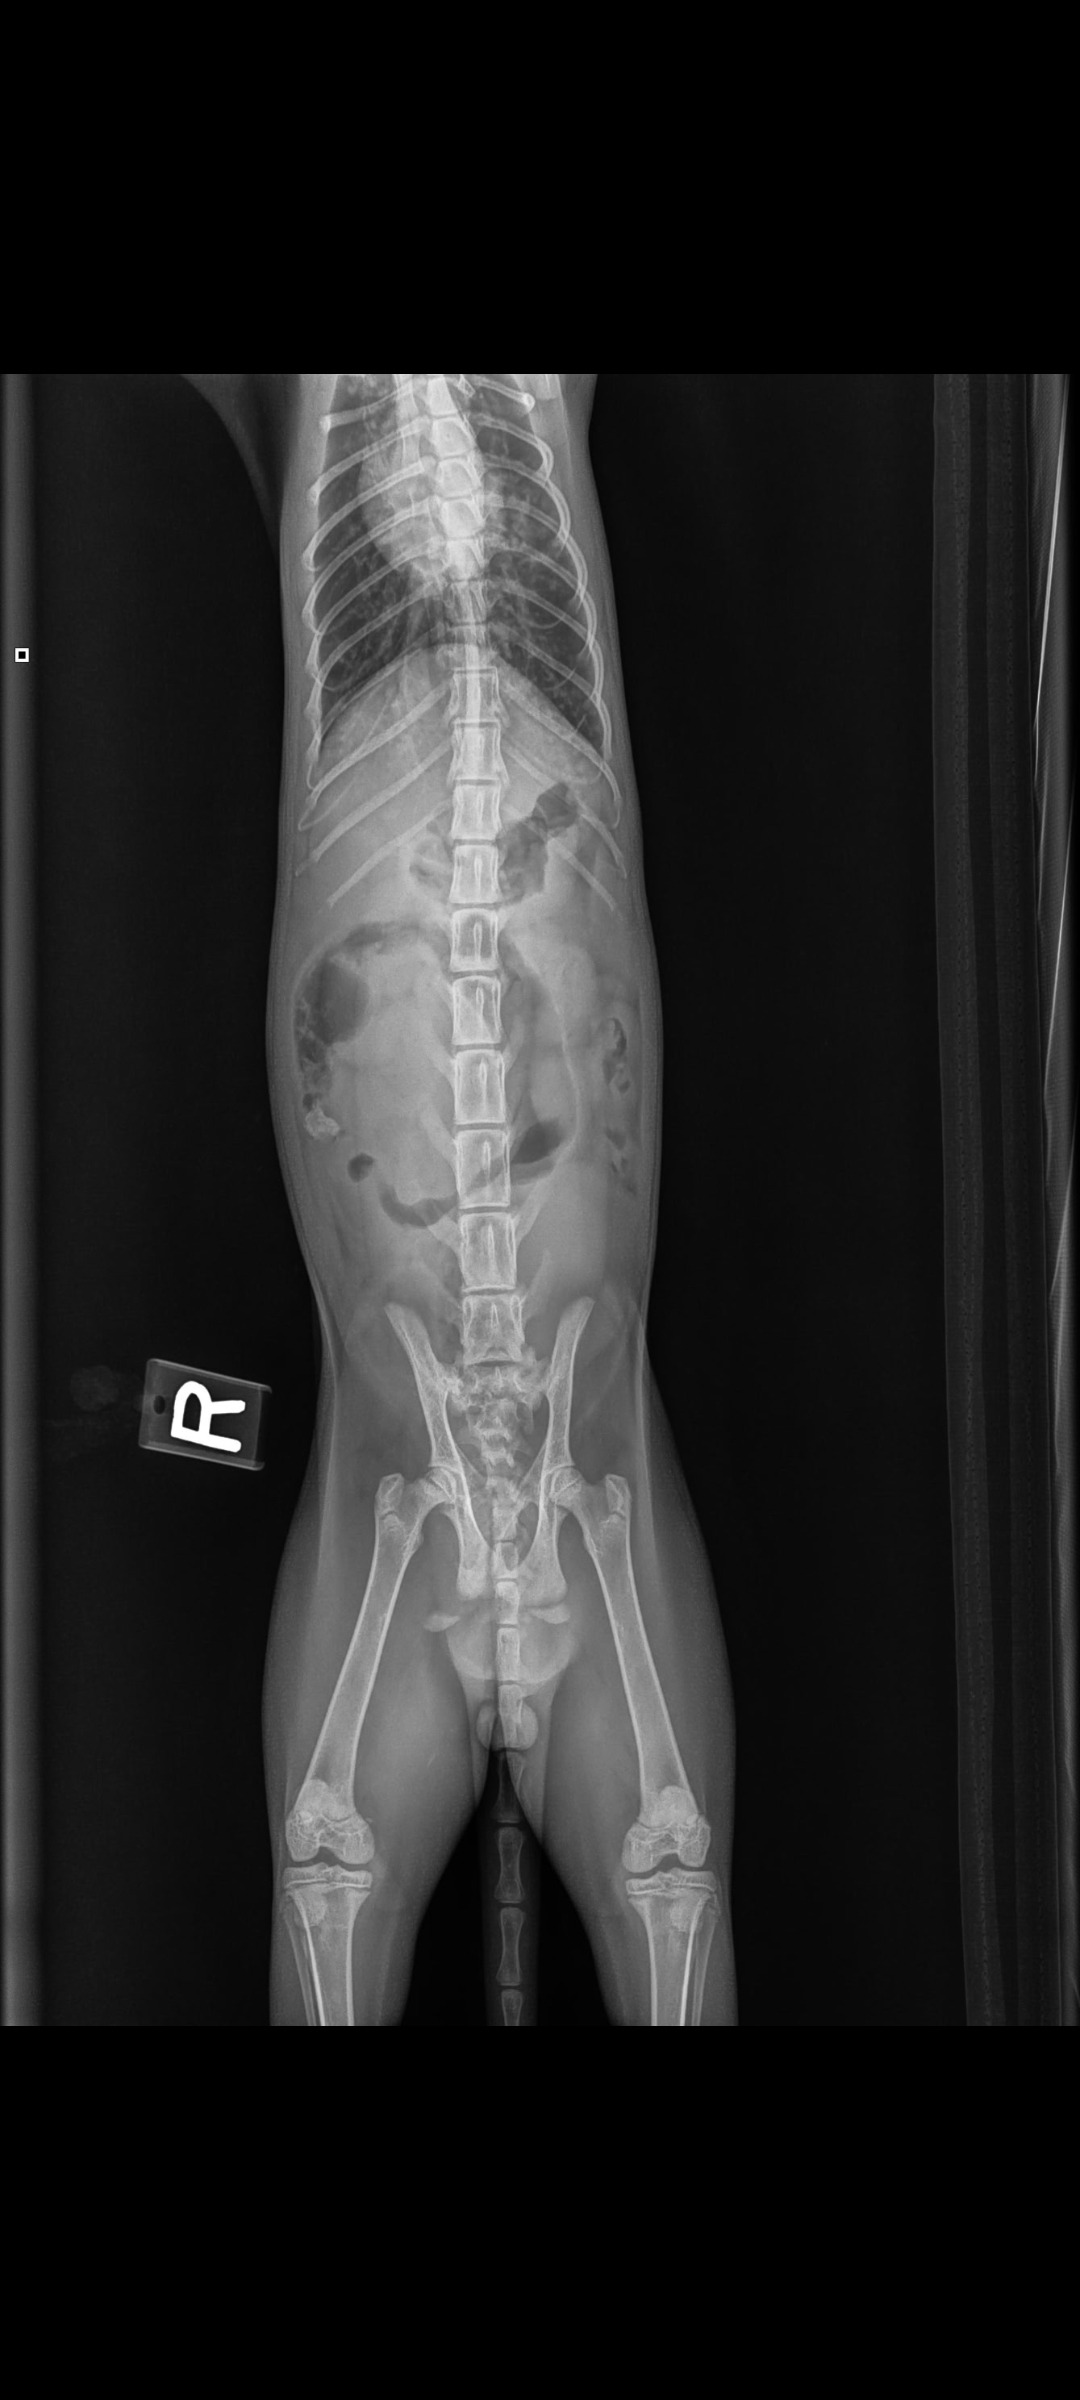

He also has a fractured/broken pelvis. He is unable to walk. He is crate/cage bound for 2 weeks to minimize any movement in hopes that it heals properly but will also require physical therapy and more scans and x-rays.